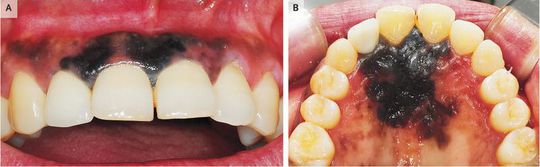

A 60-year-old woman presented with a 2-month history of black discoloration on her upper gums after blunt trauma to the mouth. She had previously been well and was a lifelong nonsmoker and nondrinker. On examination, diffuse black pigmentation was seen on both the labial and palatal sides of the anterior maxilla (Panels A and B, respectively), without tooth mobility or palpable lymphadenopathy. No bone destruction was detected on a standard dental radiograph. A hypermetabolic signal was seen in the anterior maxillary area on positron-emission tomography–computed tomography, with no metastatic spread to the lymph nodes. Incisional biopsy and histologic analysis revealed malignant melanoma. Primary malignant melanoma is uncommon in the oral cavity. Unfortunately, diagnosis may be delayed because oral malignant melanomas are frequently asymptomatic and painless in their early stages. The lesion was resected, and the patient received chemotherapy. At the last follow-up, 26 months after the initial diagnosis, she had recurrent disease and distant metastases.